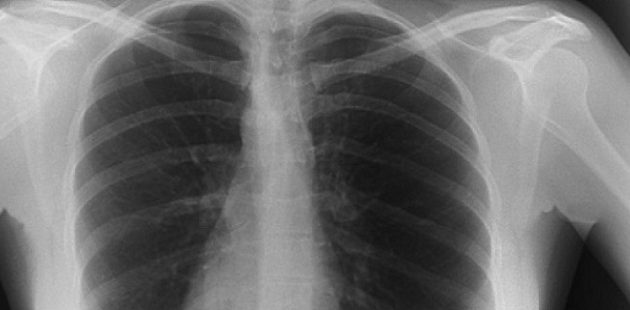

Οι πολύ παχύσαρκοι άνθρωποι χρειάζονται πολύ υψηλότερη δόση ακτινοβολίας κατά τις εξετάσεις ακτίνων-Χ, από ό,τι οι άνθρωποι κανονικού βάρους, με αποτέλεσμα να έχουν υπερδιπλάσιο κίνδυνο καρκίνου, σύμφωνα με μια νέα βρετανική επιστημονική έρευνα.

Οι ερευνητές, με επικεφαλής την αναπληρώτρια καθηγήτρια Κάρεν Ναπ του Πανεπιστημίου του Έξετερ, που έκαναν τη σχετική δημοσίευση στο ακτινολογικό περιοδικό Journal of Radiological Protection, μελέτησαν 630 ασθενείς που είχαν δείκτη μάζας σώματος έως 50 (ο δείκτης κανονικού βάρους είναι έως 25).

Διαπιστώθηκε ότι τα εν λόγω υπερβολικά παχύσαρκα άτομα χρειάζονταν πολύ ισχυρότερη ακτινοβολία κατά τις ακτινογραφίες εξαιτίας της αυξημένης ποσότητας ιστών που έπρεπε να απεικονιστεί.

Ο κίνδυνος καρκίνου λόγω της έξτρα ακτινοβολίας υπολογίστηκε ότι ήταν κατά μέσο όρο 153% μεγαλύτερος σε σχέση με τους ανθρώπους κανονικού βάρους. Όμως ο απόλυτος κίνδυνος καρκίνου παραμένει χαμηλός.

Η δόση της ακτινοβολίας κατά τις ακτινογραφίες προσαρμόζεται από τους ακτινολόγους ανάλογα με το βάρος του εξεταζόμενου και το όργανο προς απεικόνιση. Για παράδειγμα μια ακτινογραφία στην κοιλιά απαιτεί μεγαλύτερη δόση ακτινοβολίας από ό,τι στο στήθος.

Όσο υψηλότερη είναι η δόση, τόσο αυξάνει ο κίνδυνος πρόκλησης βλάβης στα κύτταρα, πράγμα που μπορεί να πυροδοτήσει καρκίνο.